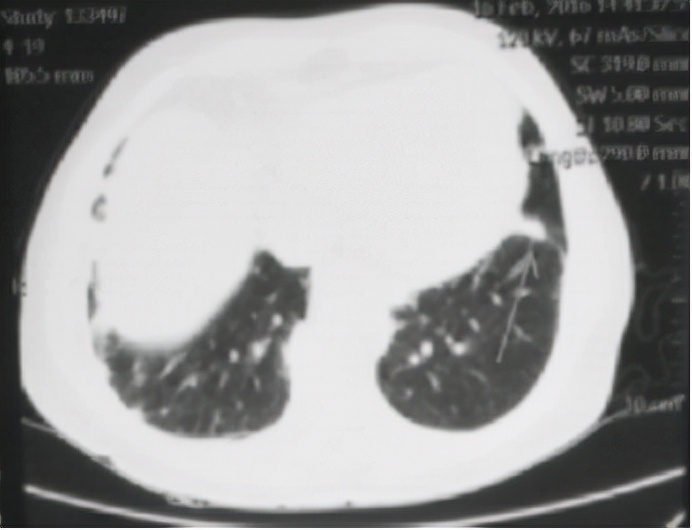

察看她随身带来的胸部CT报告,上面显示,两肺散在炎症,左肺下叶小结节 ( 见下图 ) 。

接着察看了她的舌象和脉象:舌偏红苔薄,脉小弦细。四诊合参我辨证冯女士为风痰犯肺,邪郁化热。治宜祛风化痰,清肺止咳。